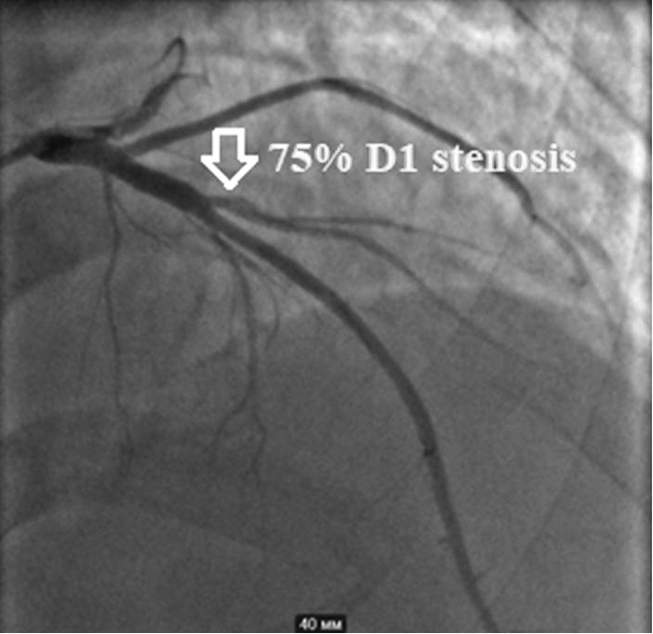

Taking into account his dyspnea on exertion and reduced exercise tolerance, the patient underwent coronary angiography, which revealed 75% proximal stenosis of the diagonal branch (D1) of his left anterior descending artery (LAD). His left circumflex coronary artery and right coronary artery didn’t have any significant stenosis (see Fig. 3 and 4). Conservative treatment was recommended in absence of indications for percutaneous coronary intervention (SYNTAX Score — 2 points).

Fig. 3. 75% proximal stenosis of the diagonal branch (D1) of the left anterior descending artery